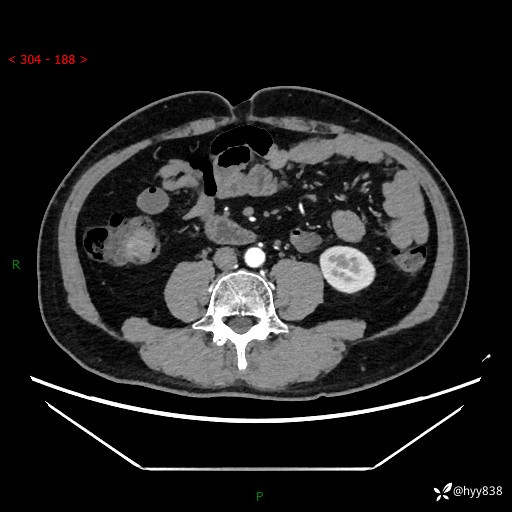

腹部CT增强扫描(外院CT平扫)

两期CT值:75hu 82hu